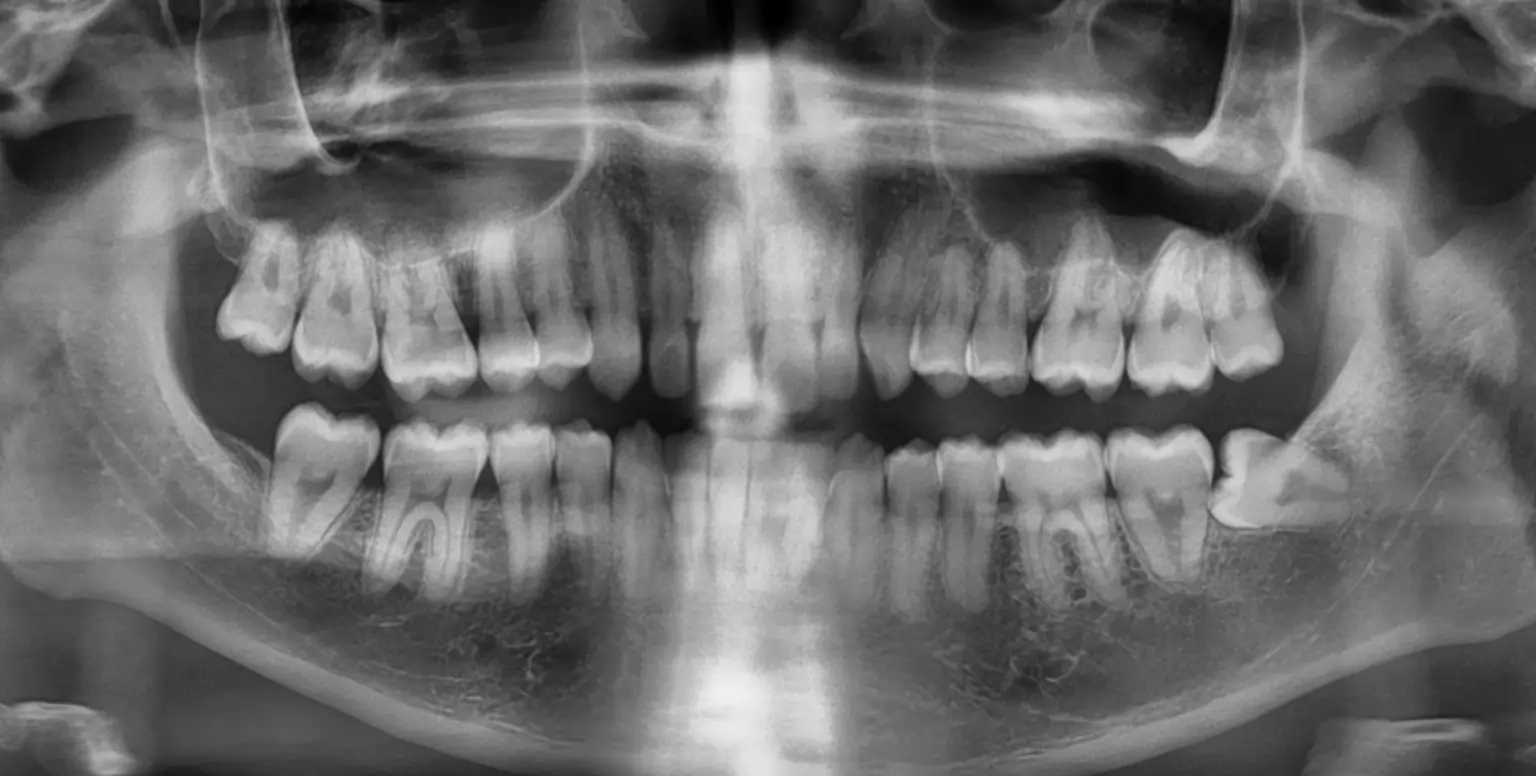

- We will assess whether there is potential for nerve damage when taking your panoramic X-ray.